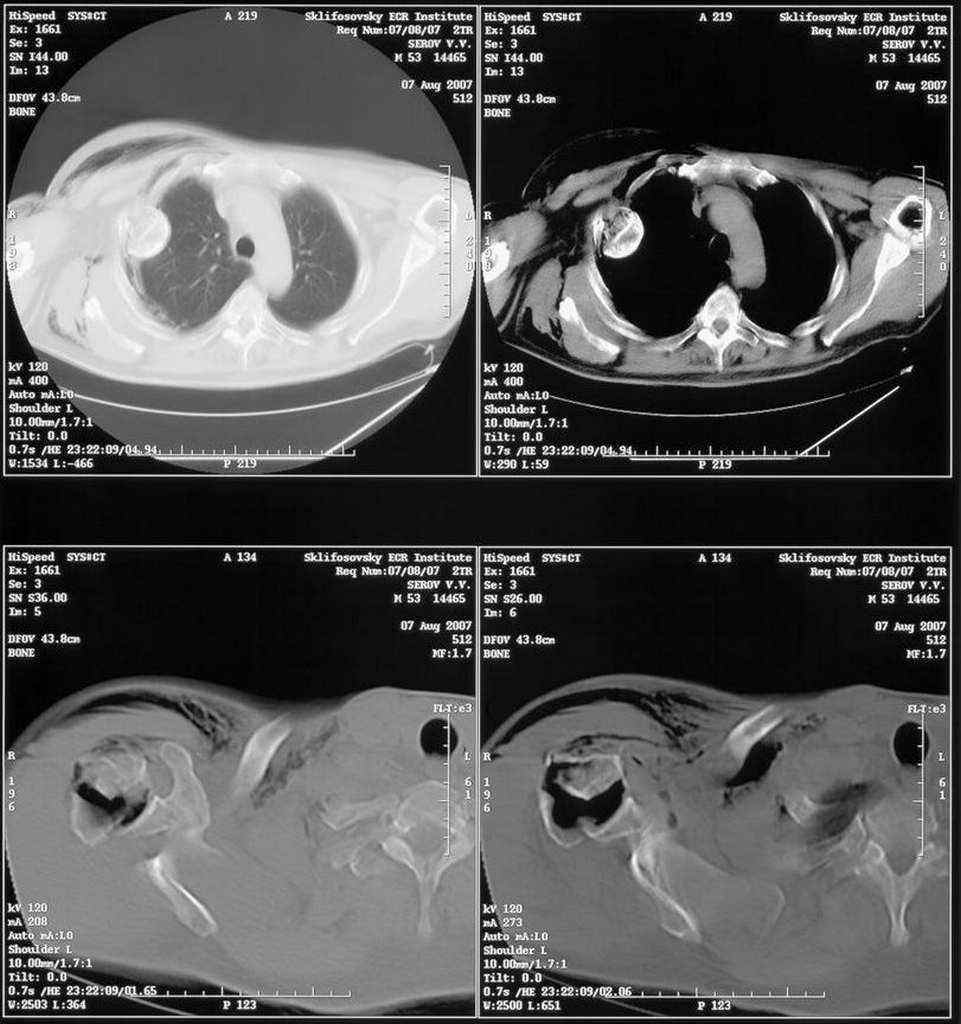

Уважаемые коллеги. Недавно из нашего отделения был выписан пациент 54 лет с закрытым переломом плечевой кости. Из анамнеза: за 2 дня до поступления в НИИСП, в состоянии алкогольного опьянения упал с лестницы на даче (высота 3-4 метра) с упором на правую руку. Через двое суток обратился за медицинской помощью. Доставлен бригадой "Скорой помощи".Правый плечевой сустав умеренно деформирован. По внутренней поверхности плеча имеется кровоподтек. При пальпации плечевого сустава имеется умеренная болезненность. Активные и пассивные движения болезненные. Снижена чувствительность по тыльной поверхности пальцев кисти и отсутствует активное разгибание кисти и пальцев. Имеется подкожная эмфизема шеи, верхней половины грудной клетки (рис 1, 2). На рентгенограмме: оскольчатый перелом головки плечевой кости со значительным смещением, перелом 2-3 ребер справа, тканевая эмфизема (рис 3). КТ при поступлении: перелом головки плечевой кости в области анатомической шейки со смещением отломка головки в грудную полость, правосторонний гидроторакс, перелом 2-3-4 ребер справа. (рис 4). Через двое суток после поступления выполнена операция: атипичная торакотомия, эвакуация свернувшегося гемоторакса, удаление инородного тела (головки плечевой кости) из плевральной полости (при этом выявлено имеющееся повреждение париетального и висцерального листков плевры) (рис. 5), дренирование плевральной полости, замещение проксимального конца плечевой кости спейсером из костного цемента с антибиотиком (рис. 6). Послеоперационный период протекал гладко. При контрольной рентгенографии положение спейсера удовлетворительное (рис. 7, 8). Дренаж из плевральной полости удален через 3 суток после вмешательства. Послеоперационная рана зажила первичным натяжением. Через 12 дней после операции больной выписан на амбулаторное лечение.